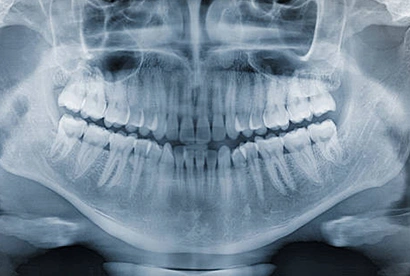

Panoramic X-rays

Panoramic radiography allows us to capture the entire mouth in a single image, including the teeth, both upper and lower jaws, and any surrounding structures or tissues. We commonly use this machine to learn crucial information about the positions of certain teeth, irregularities in the gum and bone, and as a planning tool for full and partial dentures and implants.